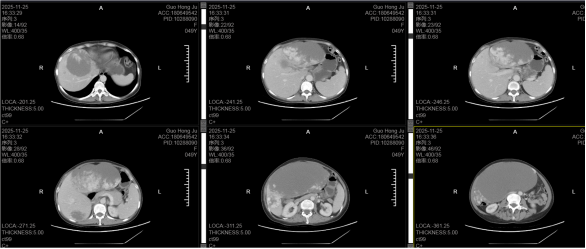

“肝脏这个30×25厘米巨大肿瘤,占据腹腔近70%空间,这就像在布满血管的‘豆腐’上剥离一块巨大的‘石头’,稍有不慎就会引发大出血,甚至导致患者死亡。”肝胆胰外科温江涛介绍。手术当日,手术室全程处于“高压模式”:肿瘤与肝实质粘连紧密,血管网络错综复杂,肝胆外科团队及手术室团队凭借精湛的解剖技术与默契的配合,在聚光灯下一点点分离粘连组织,精准结扎每一根滋养血管,避免损伤肝门静脉、肝动脉等核心血管。最终历经2小时奋战,这枚困扰患者多年的“肝脏炸弹”被完整切除,用无菌布巾裹住瘤体,合力将这个15公斤的“肉球”缓缓移出腹腔,术中出血量控制在最低范围,患者生命体征始终平稳。

最关键的“生命保障”来自自体血回输技术的创新应用。术中,患者肝血管瘤中储存的血液及剥离过程中流失的血液被实时收集,经设备过滤、洗涤、离心后,将红细胞等有效成分分离出来,即时回输到患者体内。相当于把患者自己的血“净化后再利用”,不仅避免了血源紧张的困境,还杜绝了异体输血可能引发的过敏、感染等风险。此次手术共回收并回输自体血800毫升,相当于为患者“省下”了近4袋全血,成为手术成功的关键支撑。

术中肝巨肿物实物图及自体血回输系统